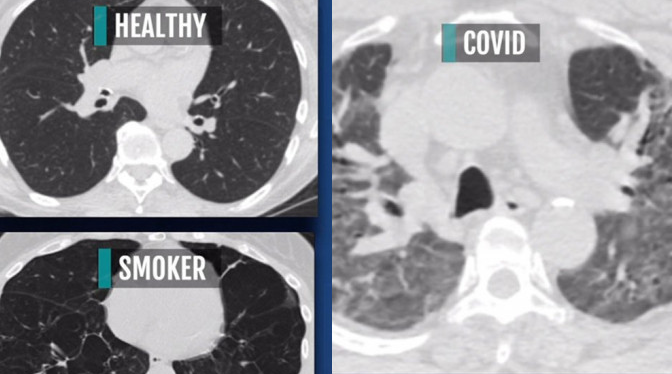

米蕭德對比3張斷層掃瞄影像,分別為一般人、吸煙者,以及新冠患者的肺部狀態。她指出,一般人的肺部X光片應該是大部分呈現黑色,代表充滿空氣;而吸煙者的肺部則有部分白點;至於新冠肺炎患者的肺部,則幾乎是一片白色的嚴重「傷疤」,並指這些白色「傷疤」就像是混凝土,會影響氧氣進入肺部。

而很多無症狀感染患者的檢查結果也出現嚴重的肺部損傷,並留下疤痕。

她形容新冠肺炎患者就像是得了末期肺病,嚴重程度就像是吸煙數十年的人,唯一的區別是在時間上,新冠肺炎只是幾天的事。